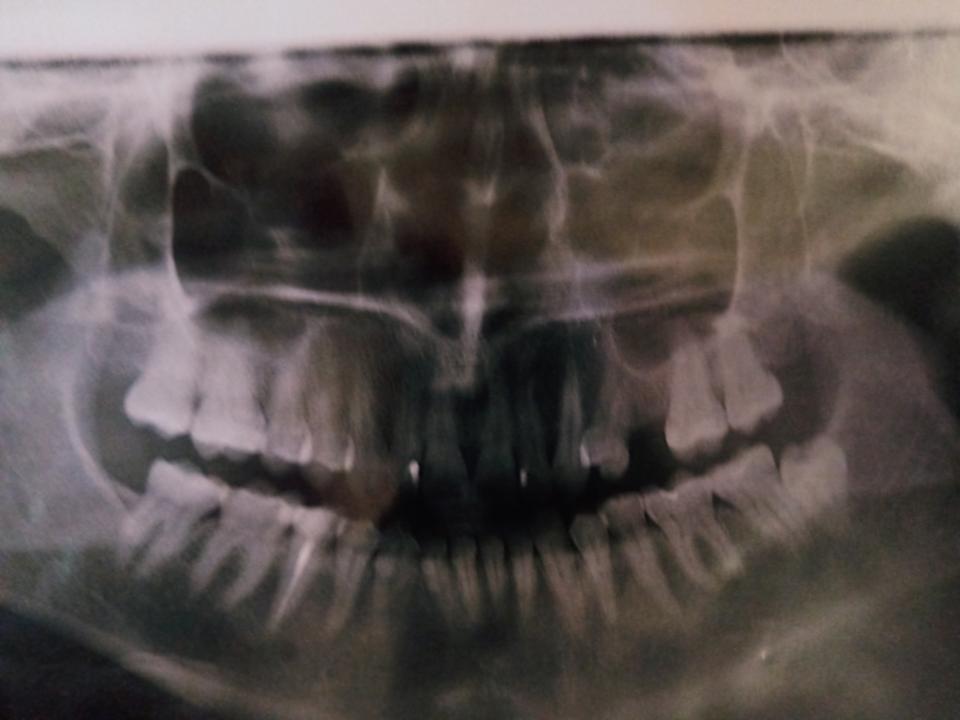

Сделали панорамный снимок. Сходила на прием к хирургу в стоматологический центр.

На что похоже ? Как правильно действовать ? что видно по снимку, если видно ?

Затемнения, конечно, вижу какие-то, но не могу делать выводы.

А учитывая клиническую картину вообще запутался

Плохо видно как раз проблемный участок. Надо прозондировать пародонт зубов,возможно появился карман и теперь симптоматика пульпита. Сделать фриз тест зубов,посмотреть на секундный интервал возникновения боли,через 2-3 сек боль проходит у здорового зуба. В Днепре клиника доктора Неженцева ,доктор Квакуша. Мотнитесь на консультацию.